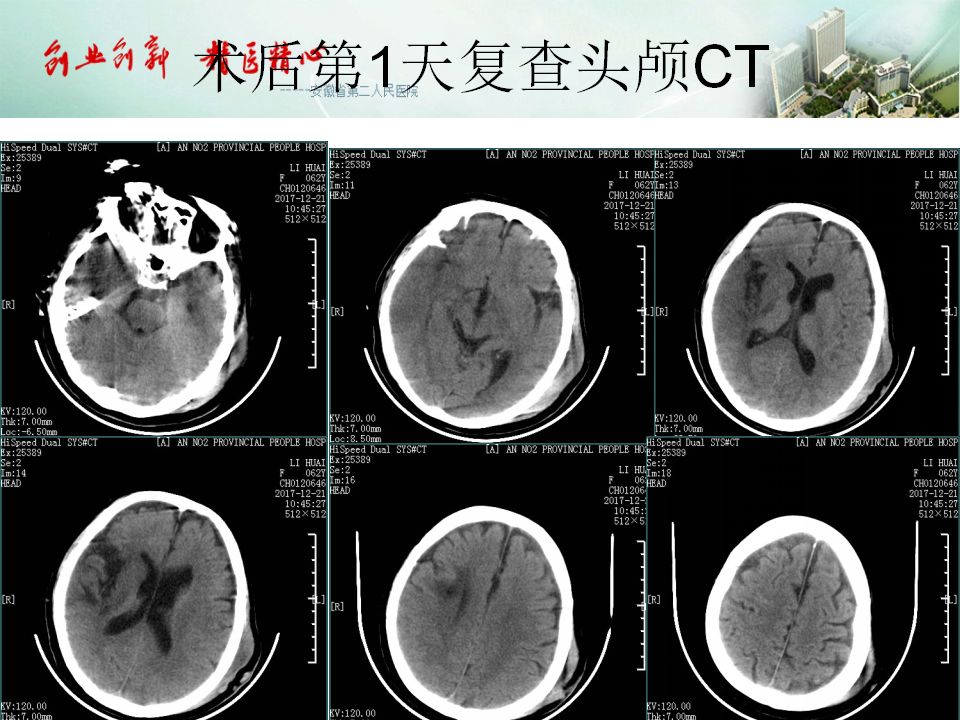

今天为大家分享的是“强生医疗CNV-神经介入专栏”第五十一期,由安徽省第二人民医院神经内科陈长春主任医师带来的“急性缺血性脑卒中超早期治疗--通与不通的哲学思考”精彩PPT,欢迎观看。文章仅代表作者个人观点,如有不同见解,欢迎同道斧正!